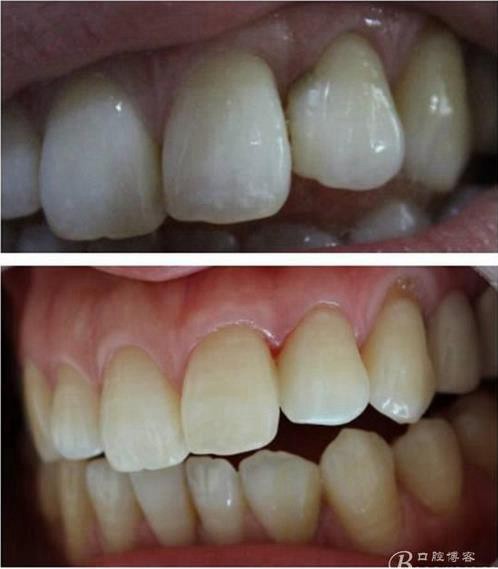

(這個(gè)是這個(gè)是學(xué)后第一次做美學(xué)修復(fù))

第一次做嵌體是樹(shù)脂嵌體。做完之后我跟我們主任炫耀,本來(lái)是想讓他夸我一下的。沒(méi)想到他說(shuō):“別高興太早,咱們時(shí)間上看。”說(shuō)實(shí)話(huà)當(dāng)時(shí)心里一點(diǎn)底沒(méi)有,到底能用多長(zhǎng)時(shí)間,自己一點(diǎn)沒(méi)底。